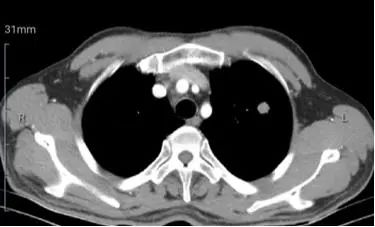

2019年9月6日复查肝功、肾功、血凝均正常;HBsAg 1786 IU/ml,HBeAg 7.74 IU/ml,hsHBV-DNA 10 IU/ml,AFP 15.97ng/ml。ECT:右侧第4、6、7肋骨及左侧第6肋骨代谢异常,建议随诊。上腹部MR增强:肝S7段可见动脉期明显结节样强化,门脉期及延迟期呈轻度强化灶(图1)。胸部增强CT: 左肺上叶1.5cm结节样高密度影,形态欠规则,边界清,增强扫描呈不均匀轻度强化。考虑肿瘤性病变:1. 原发支气管肺癌(小细胞肺癌)?2. 转移?(图2)。建议行肺穿刺活检或胸外科手术明确病灶性质,患者拒绝。

图2. 2019年9月6日胸部强化CT示左肺上叶结节样高密度影